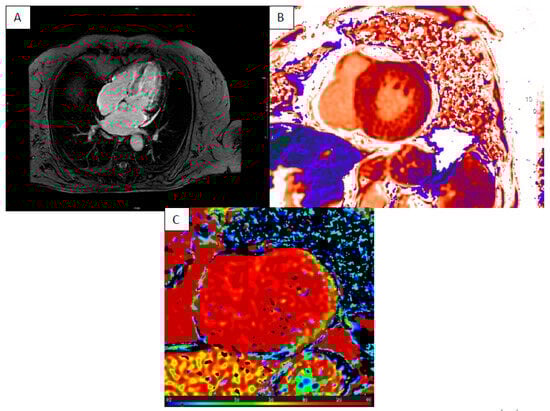

4. Cardiac Amyloidosis